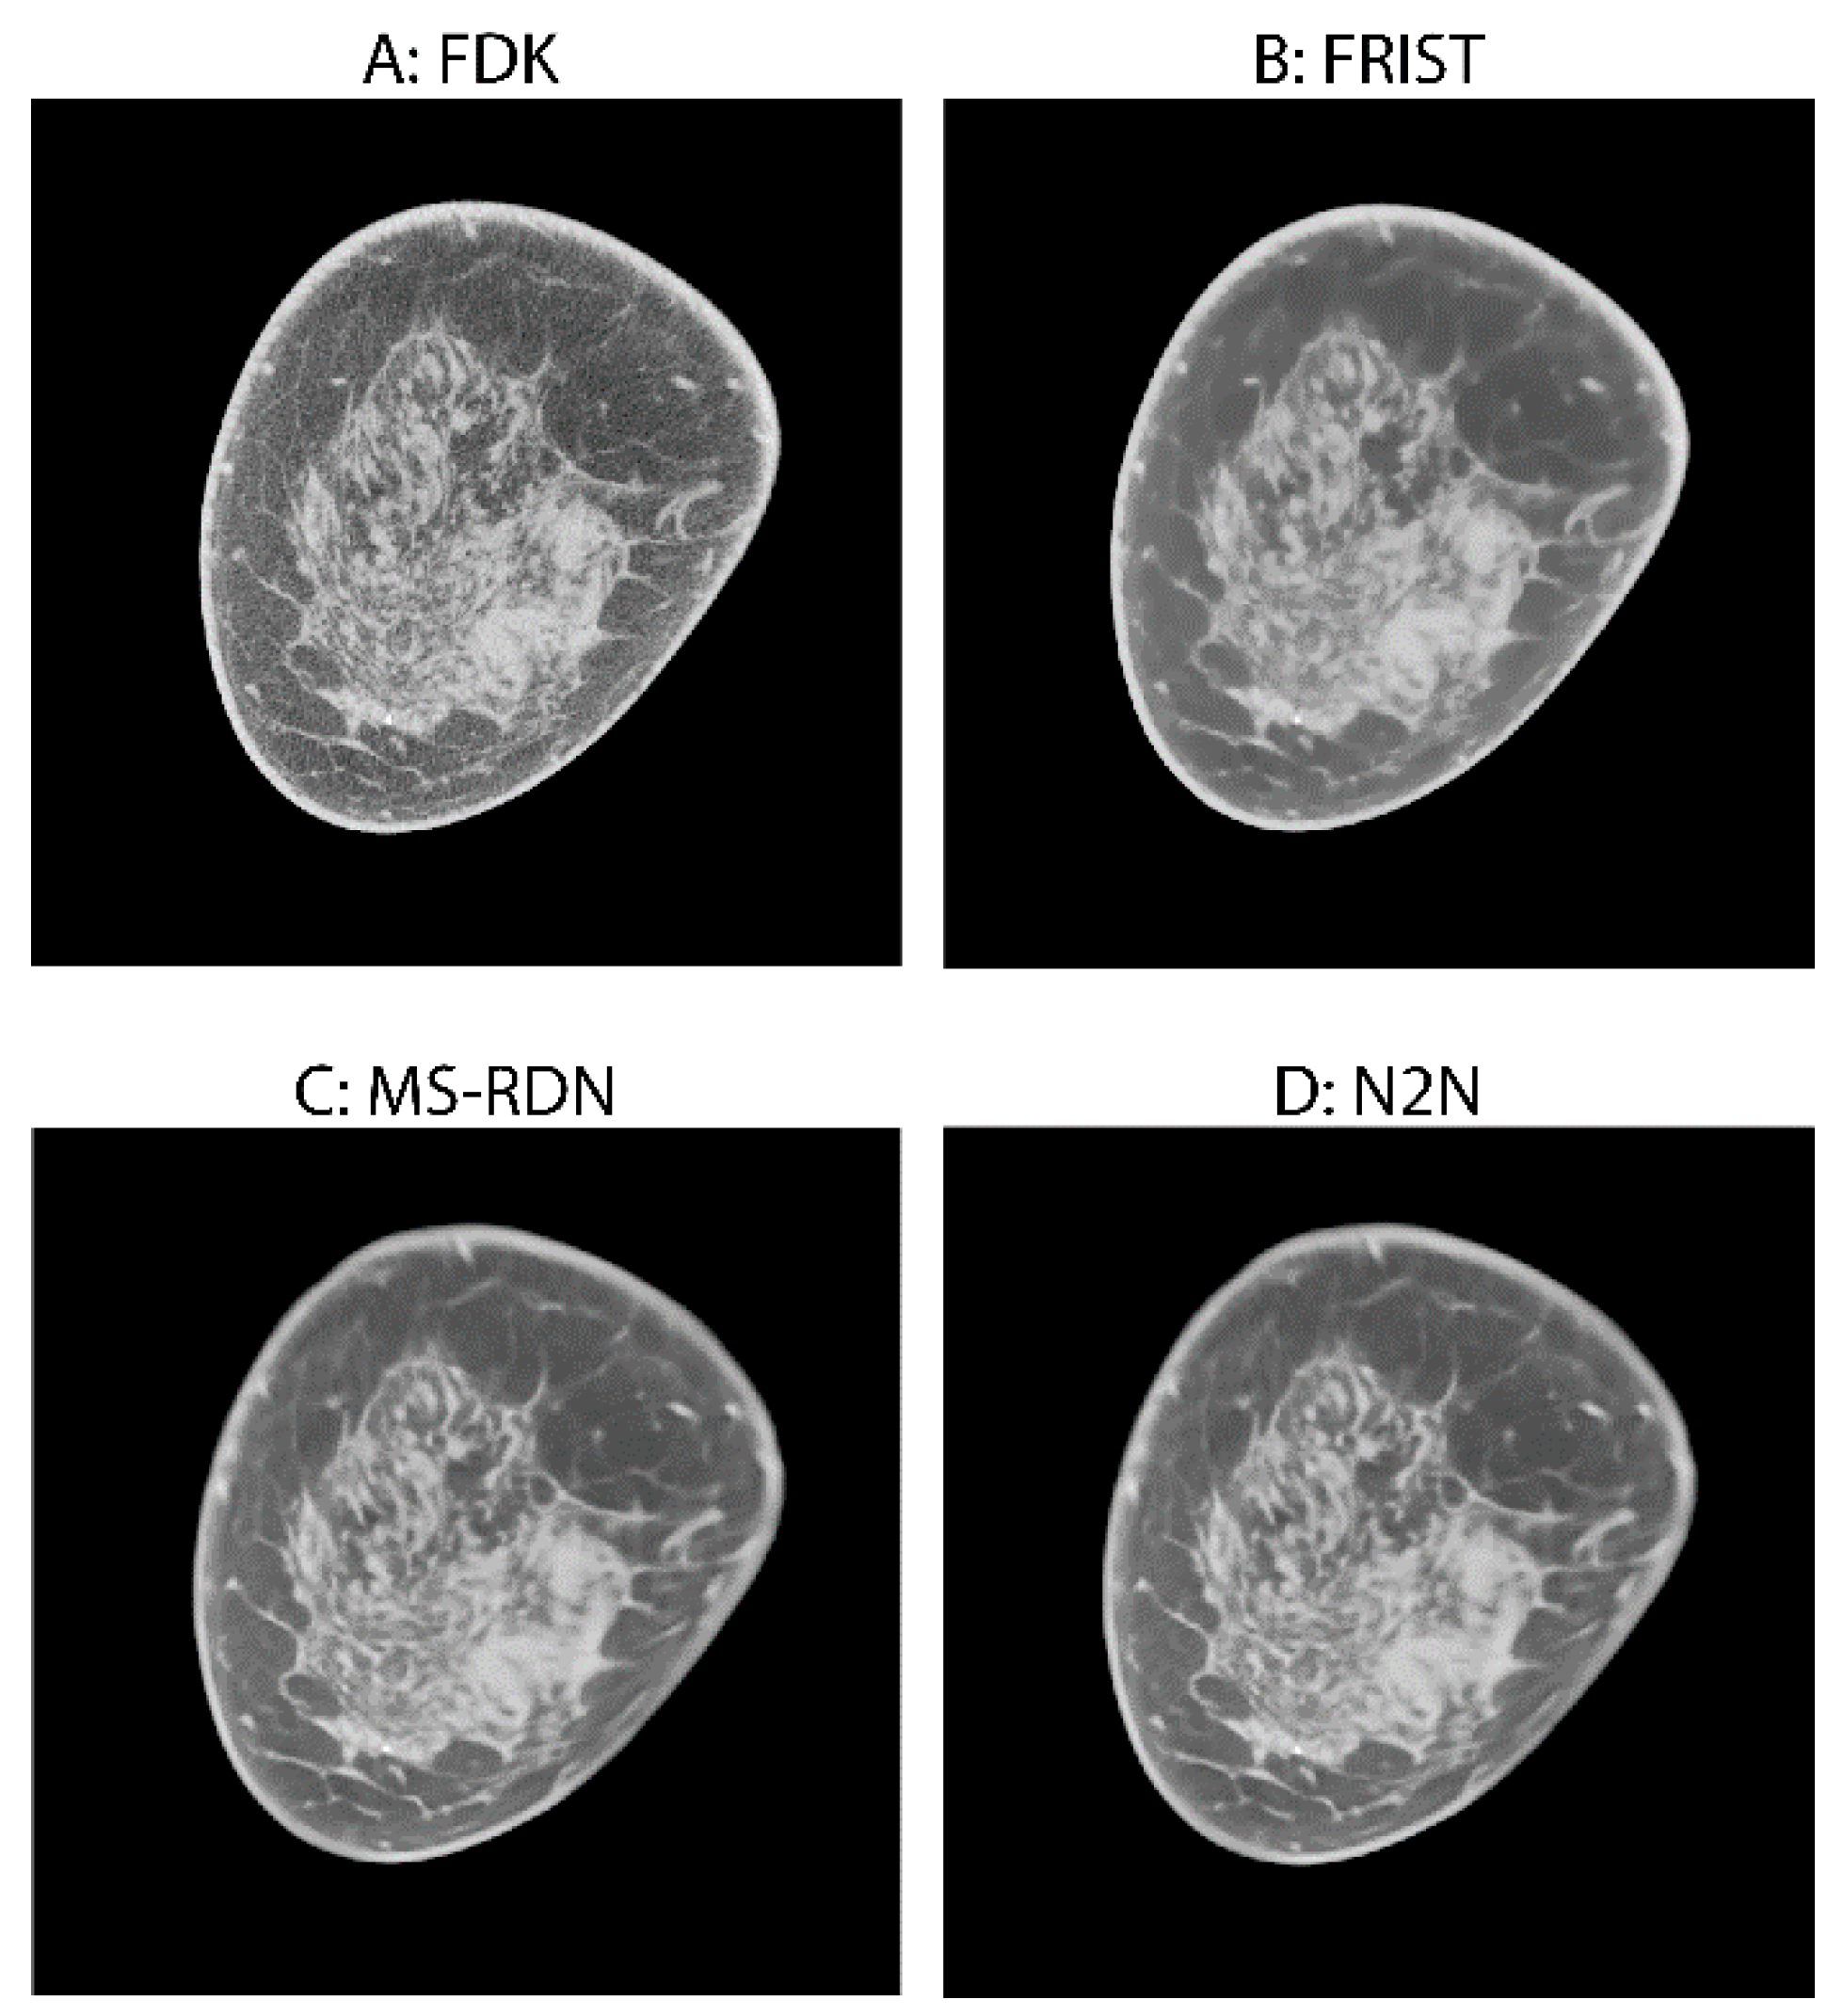

- Fu, Z.; Tseng, H.W.; Vedantham, S.; Karellas, A.; Bilgin, A. A residual dense network assisted sparse view reconstruction for breast computed tomography. Sci. Rep. 2020, 10, 21111. [Google Scholar] [CrossRef]